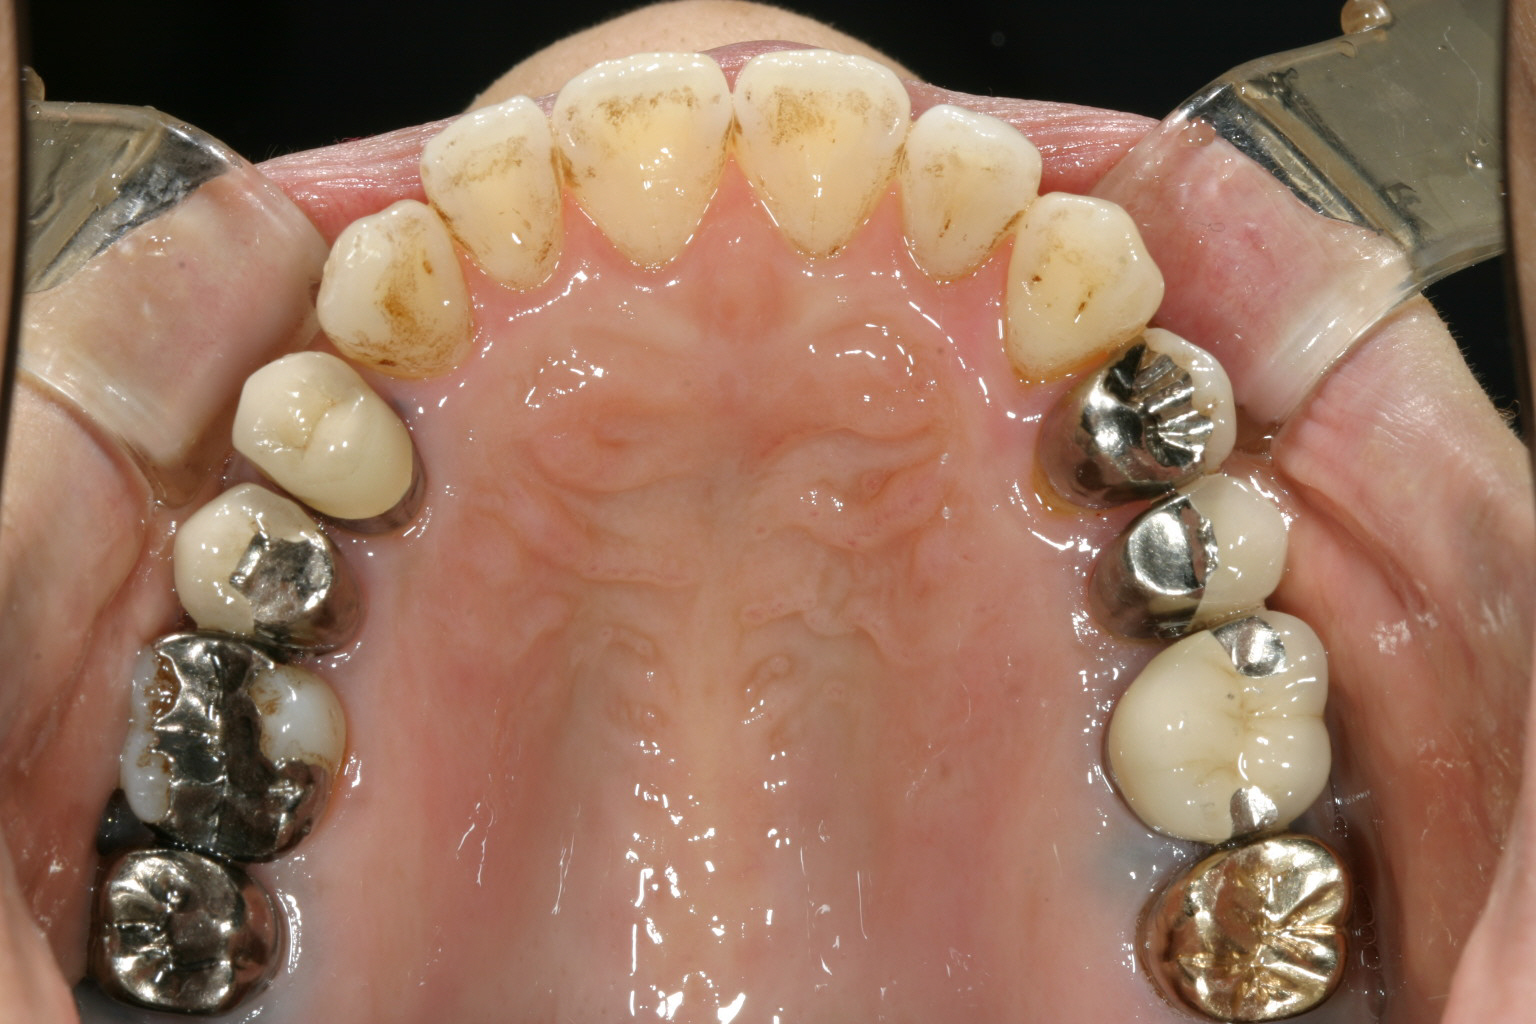

歯の乱れは大した事無いのですが補綴物が多くて治療は大変です。

下顎も補綴物が多く又前歯部にガタガタが見受けられます。